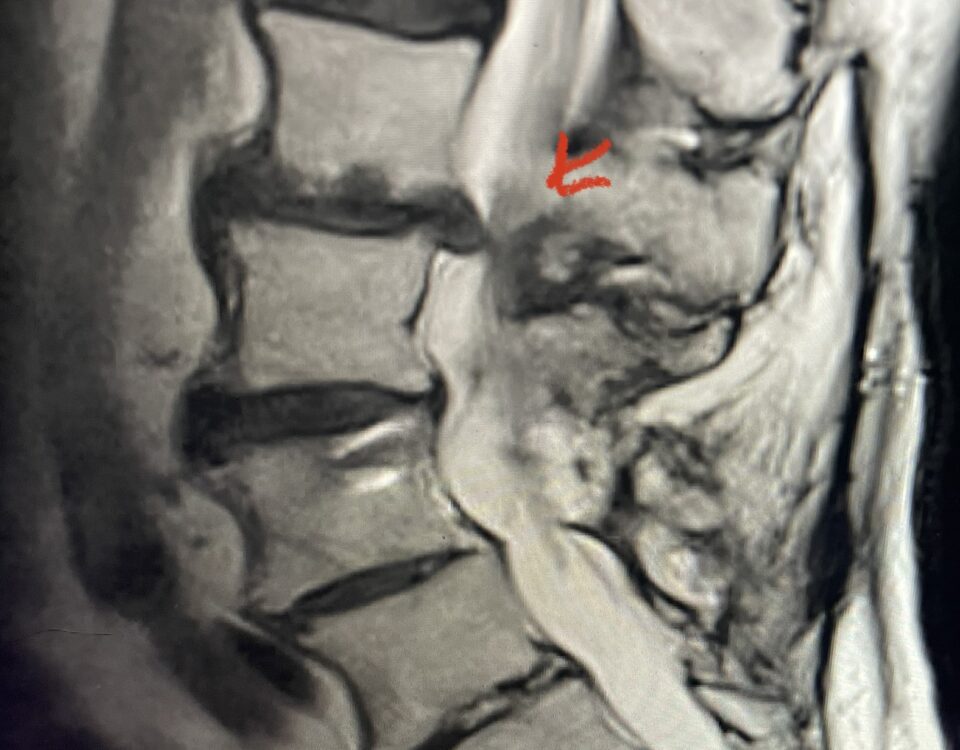

The spinal synovial cyst is one of the most interesting expressions of spinal instability. They emanate from the synovial lining of a degenerated facet joint that […]